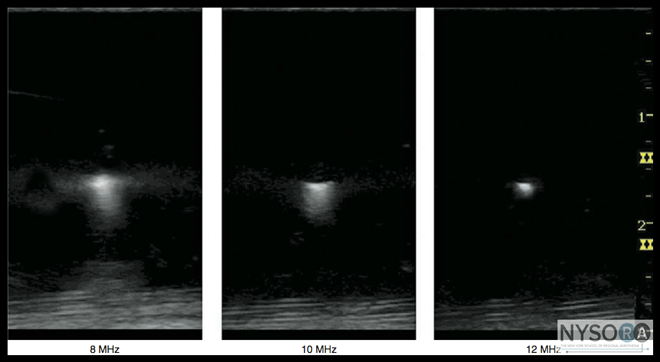

Figure 3: The piezoelectric effect. Mechanical deformation and consequent oscillation caused by an electrical field applied to certain material can produce a sound of high frequency. Acoustic velocity is the speed at which a sound wave travels through a medium. It is equal to the frequency times the wavelength. Speed is determined by the density (ρ) and stiffness (κ) of the medium (c = (κ/ρ)1/2). Density is the concentration of medium. Stiffness is the resistance of a material to compression. Propagation speed increases if the stiffness is increased or the density is decreased. The average propagation speed in soft tissues is 1540 m/s (ranges from 1400 m/s to 1640 m/s). However, ultrasound cannot penetrate lung or bone tissues. Acoustic impedance(z) is the degree of difficulty demonstrated by a sound wave being transmitted through a medium; it is equal to density ρ multiplied by acoustic velocity c (z = ρc). It increases if the propagation speed or the density of the medium is increased. Attenuation coefficient is the parameter used to estimate the decrement of ultrasound amplitude in a certain medium as a function of ultrasound frequency. The attenuation coefficient increases with increasing frequency; therefore, a practical consequence of attenuation is that the penetration decreases as frequency increases (Figure 4). Ultrasound waves have a self-focusing effect, which refers to the natural narrowing of the ultrasound beam at a certain travel distance in the ultrasonic field. It is a transition level between near field and far field. The beam width at the transi- tion level is equal to half the diameter of the transducer. At the distance of two times the near-field length, the beam width reaches the transducer diameter. The self-focusing effect amplifies ultrasound signals by increasing acoustic pressure. In ultrasound imaging, there are two aspects of spatial resolution: axial and lateral. Axial resolution is the minimum separation of above-below planes along the beam axis. It is determined by spatial pulse length, which is equal to the product of wavelength and the number of cycles within a pulse. It can be presented in the following formula: Axial resolution = wavelength (λ) × number of cycle per pulse (n) ÷ 2 The number of cycles within a pulse is determined by the damping characteristics of the transducer. The number of cycles within a pulse is usually set between 2 and 4 by the manufacturer of the ultrasound machines. As an example, if a 2-MHz ultrasound transducer is theoretically used to do the scanning, the axial resolution would be between 0.8 and 1.6 mm, making it impossible to visualize a 21-G needle. For a constant acoustic velocity, higher frequency ultrasound can detect smaller objects and provide a better resolution image. Figure 5 shows the images at different resolutions when a 0.5-mm-diameter object is visualized with three different frequency settings. Lateral resolution is another parameter of sharpness to describe the minimum side-by-side distance between two objects. It is determined by both ultrasound frequency and beam width. Lateral resolution can be improved by focusing to reduce the beam width.

Figure 5: Ultrasound frequency affects the resolution of the imaged object. Resolution can be improved by increasing frequency and reducing the beam width by focusing. Temporal resolution is also important to observe moving objects, such as blood vessels and the heart. Similar to a movie or cartoon video, the human eye requires that the image be updated at a rate of approximately 25 times a second or higher for an ultrasound image to appear continuous. However, imaging resolution is compromised by increasing the frame rate. Optimizing the ratio of resolution to frame rate is essential to provide the best possible image. Interactions of Ultrasound Waves with Tissue